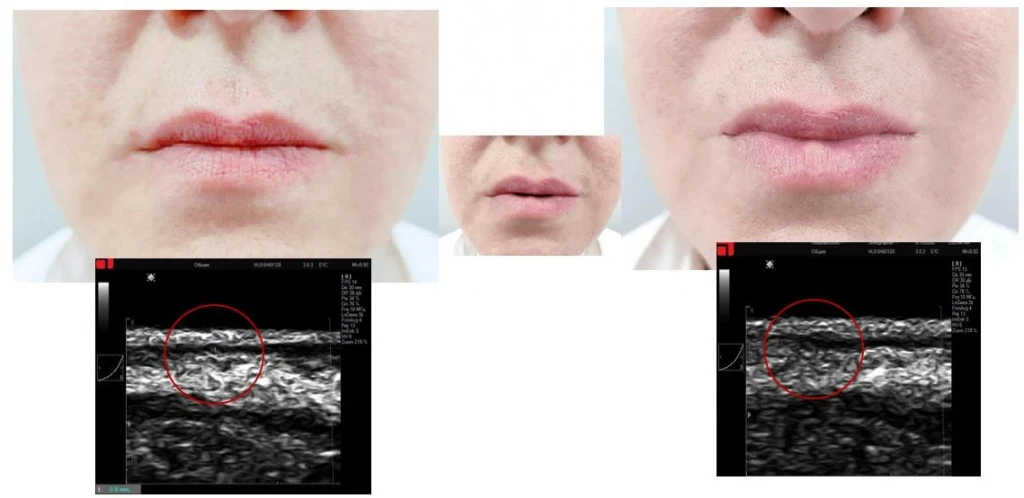

Протокол работы в зоне губ

Работа по протоколу «Lovely lips» предусматривает воздействие как с целью уменьшения объема, так и с целью его восполнения, а также устранения асимметричности их объема.

Протокол работы в зоне губ PicoCare

Рис. 5. Уменьшение объема губ по протоколу «Lovely lips» (PicoCare)

Рис. 6. Увеличение объема губ по протоколу «Lovely lips» (PicoCare)